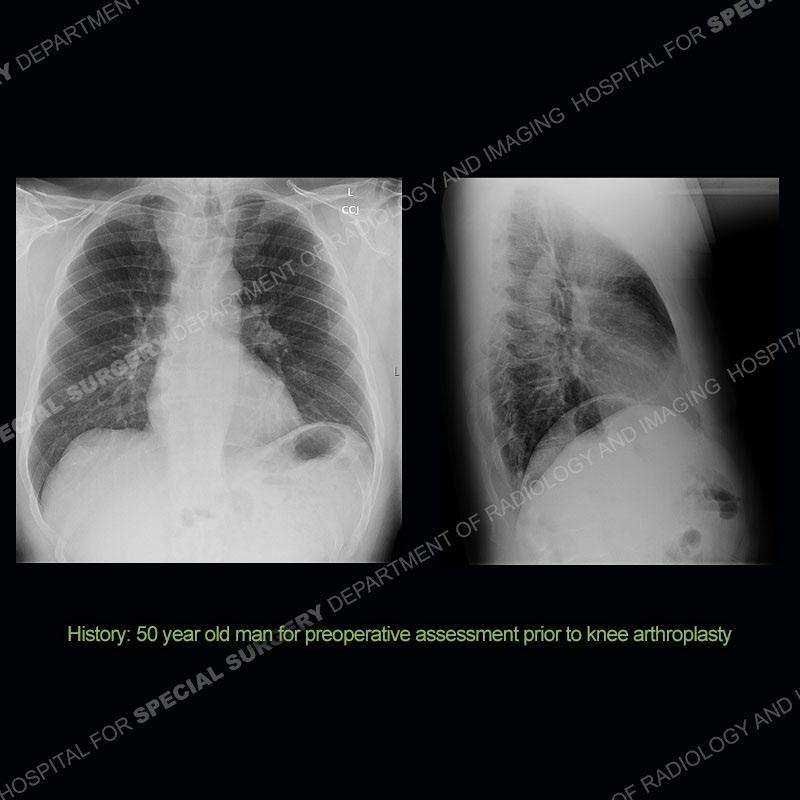

The chest radiographs demonstrate a leftward deviation of the trachea. CT images demonstrate a large, somewhat heterogeneous mass of the thyroid that extends outside the confines of the thyroid tissue. There is a subtle, enhancing soft tissue mass of the proximal right humerus. Slightly prominent mediastinal lymph nodes are present with additionally, multiple supraclavicular lymph nodes.

Over the years we have shown a couple of these cases which may be considered more so an “eye test” then anything else. In clinical practice, these are often very difficult cases as the initial finding of the tracheal deviation may be easily overlooked. Screening radiographs are clearly most often used to assess cardiopulmonary function before induction of anesthesia but at times other findings of great and unfortunately grave consequence can be found. The evaluation of the incidental thyroid mass on CT and MRI is an ever changing situation. Parameters such as age of patient, extension outside of the thyroid, enhancing nodules, and local invasion of lymph nodes are evaluated to see if a lesion needs to be further evaluated.